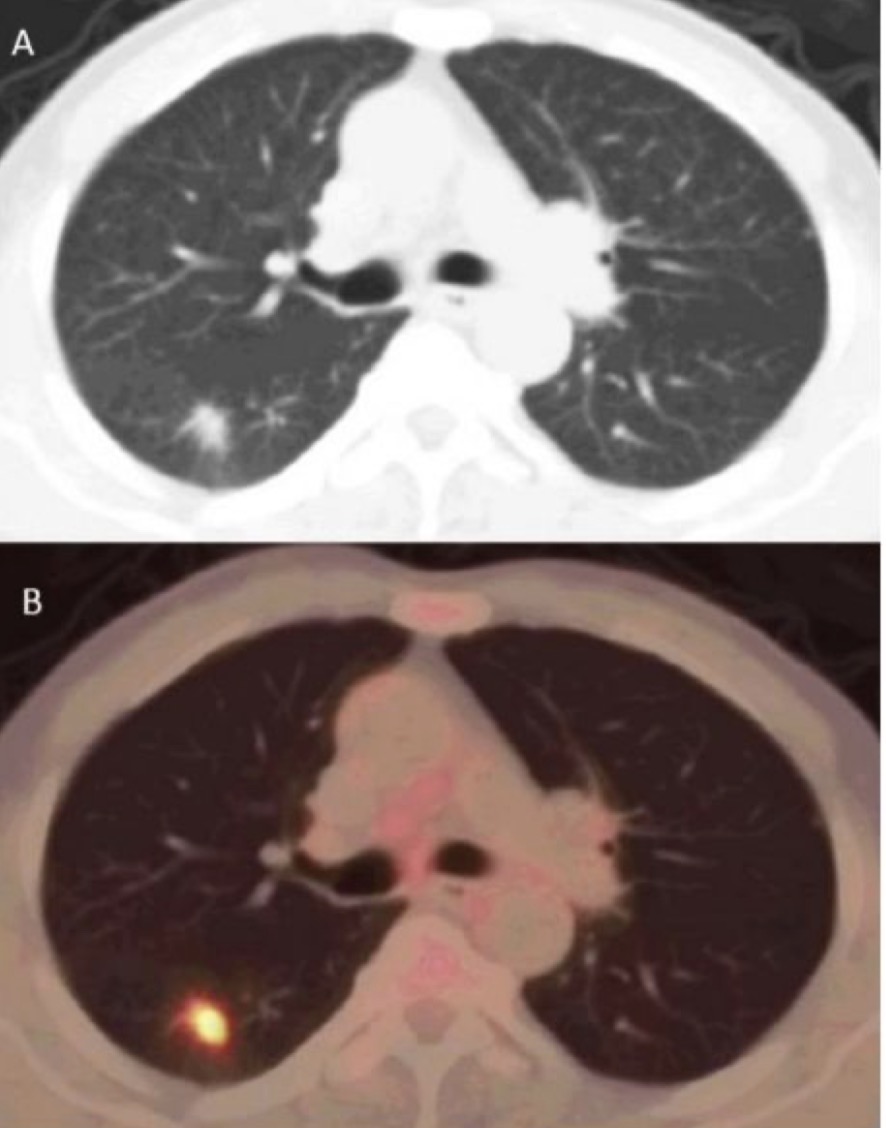

以肿瘤诊断中常用的、被誉为“世纪分子”的氟-18脱氧葡萄糖注射液(18F-FDG)为例。因恶性肿瘤细胞的代谢旺盛,导致其对葡萄糖的需求增加,因此在患者注入18F-FDG,可以使用PET-CT进行葡萄糖代谢显像,通过影像发现人体内有无异常的葡萄糖代谢高部位,从而发现病灶。

不同于CT等影像设备能够发现人体内的形态学变化,PET/CT结合核药能够帮助医生发现患者体内的代谢、细胞水平变化,能够发现更加早期、隐秘的病灶。